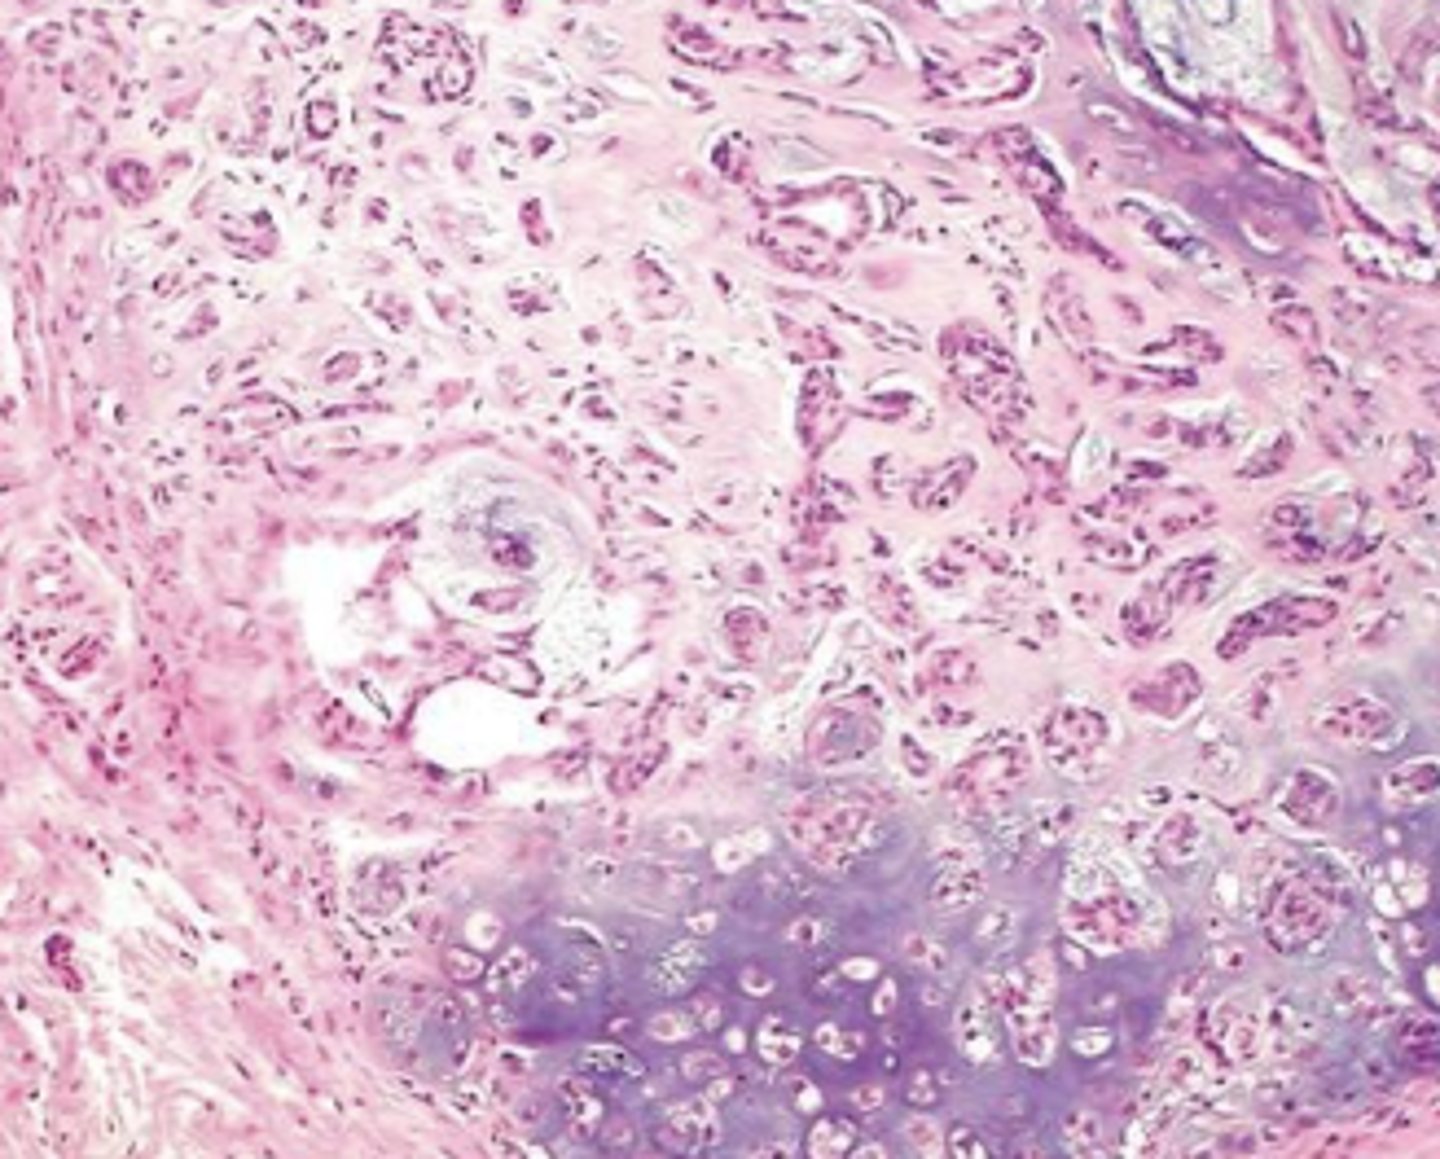

adenocarcinoma

-malignant tumor of epithelial origin

-tubular patterns on histopath

What kind of tumor is this?

schirrous response

What type of response is produced by this carcinoma?